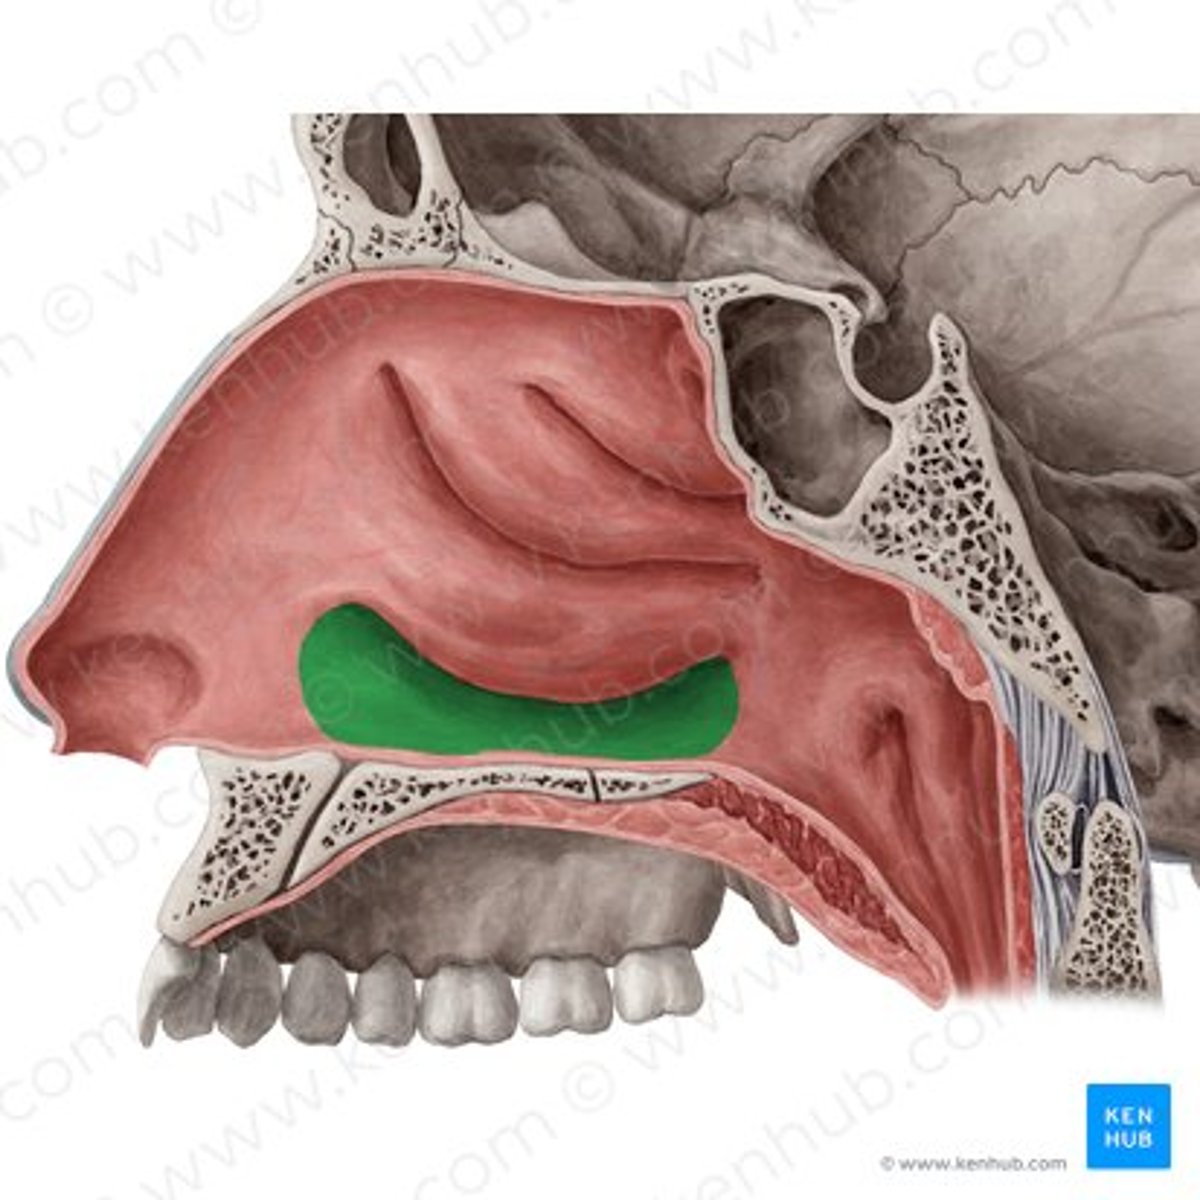

middle meatus

inferior meatus

inferior nasal concha